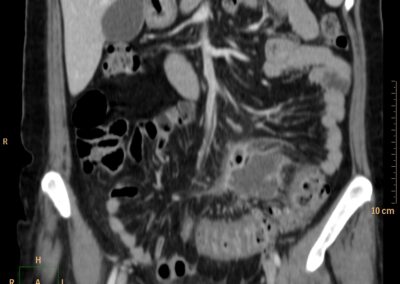

ΕΚΚΟΛΠΩΜΑΤΑ ΠΑΧΕΟΣ ΕΝΤΕΡΟΥ Posted by ΙΠΠΟΚΡΑΤΕΙΟ ΙΩΑΝΝΙΝΩΝ | Dec 16, 2020 | ΠΕΠΤΙΚΟ | 0 ΚΛΙΝΙΚΑ ΣΤΟΙΧΕΙΑ – ΙΣΤΟΡΙΚΟ υποτροπιάζοντες επαναλαμβανόμενοι πυρετοί κυρίως απογευματινές ώρες ΕΡΓΑΣΤΗΡΙΑΚΟΣ ΕΛΕΓΧΟΣ ΑΠΕΙΚΟΝΙΣΤΙΚΟΣ ΕΛΕΓΧΟΣ διακρίνονται τα αποστήματα στην ελάσσονα πύελο, καθώς και εκκολπώματα με εικόνα πάχυνσης του τοιχώματος του σιγμοειδούς ΣΥΖΗΤΗΣΗ